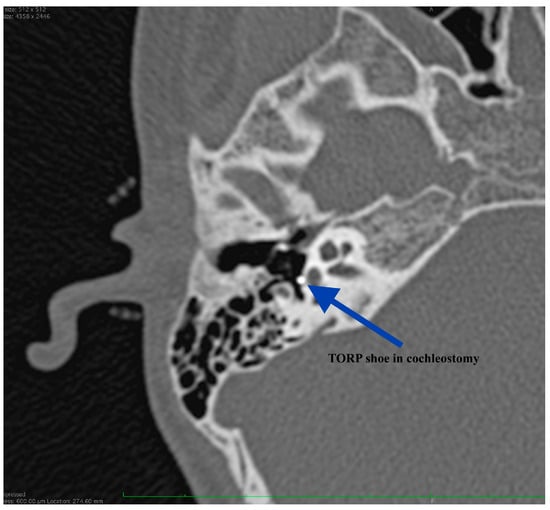

Figure 11.

CT scan at 9 months after surgery, showing proper positioning of the prosthesis: TORP shoe in the cochleostomy.

The patient reported immediate postoperative good hearing but failed to present at our Department for performing an audiogram. His hearing was firstly evaluated at 2 months after right ear surgery demonstrating an air-bone gap of 41.6 dB (from 56.6 dB preoperatively). We could not explain at that moment the results but, at 9 months after surgery we were able to have another CT scan performed. The imaging showed good positioning of the ossicular prosthesis (Figure 10 and Figure 11). Without surgical investigation of the middle ear is it impossible to know the precise reason why the hearing restoration is not as good as we expected. We can hypothesize about local healing changes but we cannot be sure.